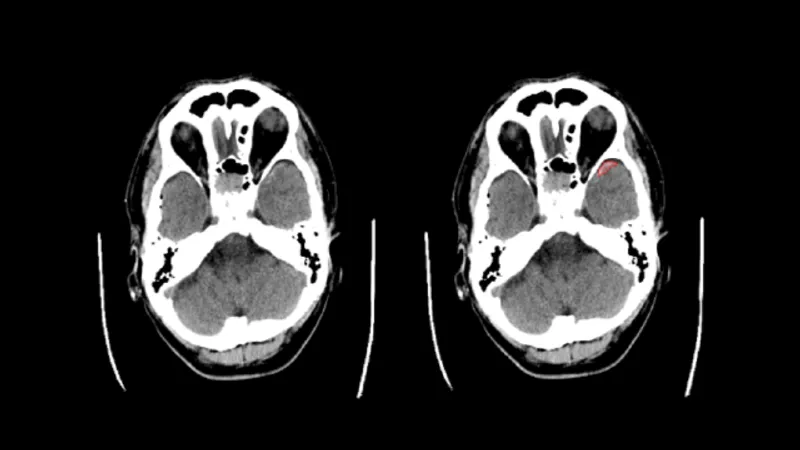

頭部CT画像から 高吸収/低吸収領域及び組織構造・境界の不明瞭化がみられる領域の抽出

頭部単純 CT 画像情報から高吸収・低吸収領域、組織構造・境界の不明瞭化領域の抽出を行います。

頭部単純 CT 画像の画像情報から、画像に基づく画素値の分析を行い、以下の情報を提供します。 (1) 頭蓋内で周囲及び前後のスライスと比べ高吸収の領域 (2) 頭蓋内で周囲及び前後のスライスと比べ低吸収の領域 (3) 頭蓋内で前後のスライス及び同一スライス内の左右で比較して組織構造もしくは組織境界